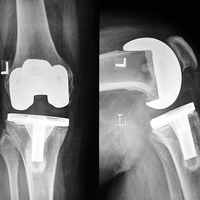

Case:2 TKR

Arthroscopy Surgeon in Ahmedabad

Post-Op